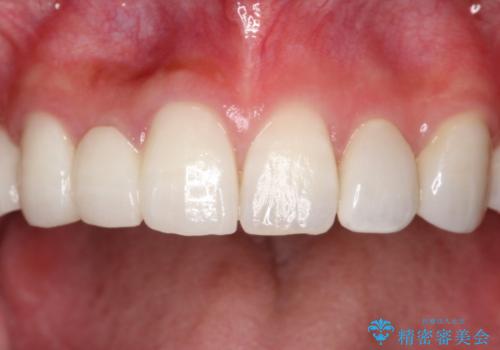

金属を使わないセラミックへ変更することで、自然な見た目になるとともに、ぴったりとした精度の高いかぶせ物を装着することができました。